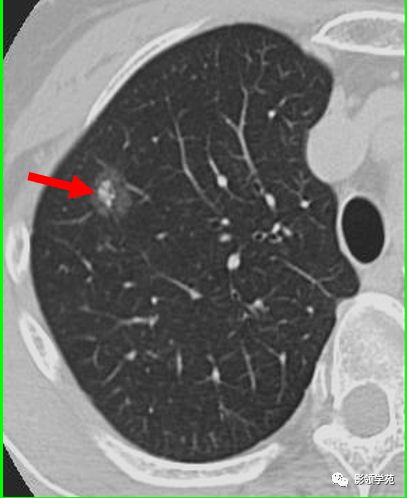

(1)较大含空洞性肿块,洞壁较厚,大于15mm,空洞外壁有分叶、毛刺,洞壁凹凸不平有壁结节,增强可见不规则强化,周围未见明显卫星病灶时,首先考虑周围型肺癌;癌性空洞洞壁一般肺门侧较厚,空洞多偏于外侧,伴有同侧淋巴结肿大更支持肺癌诊断。